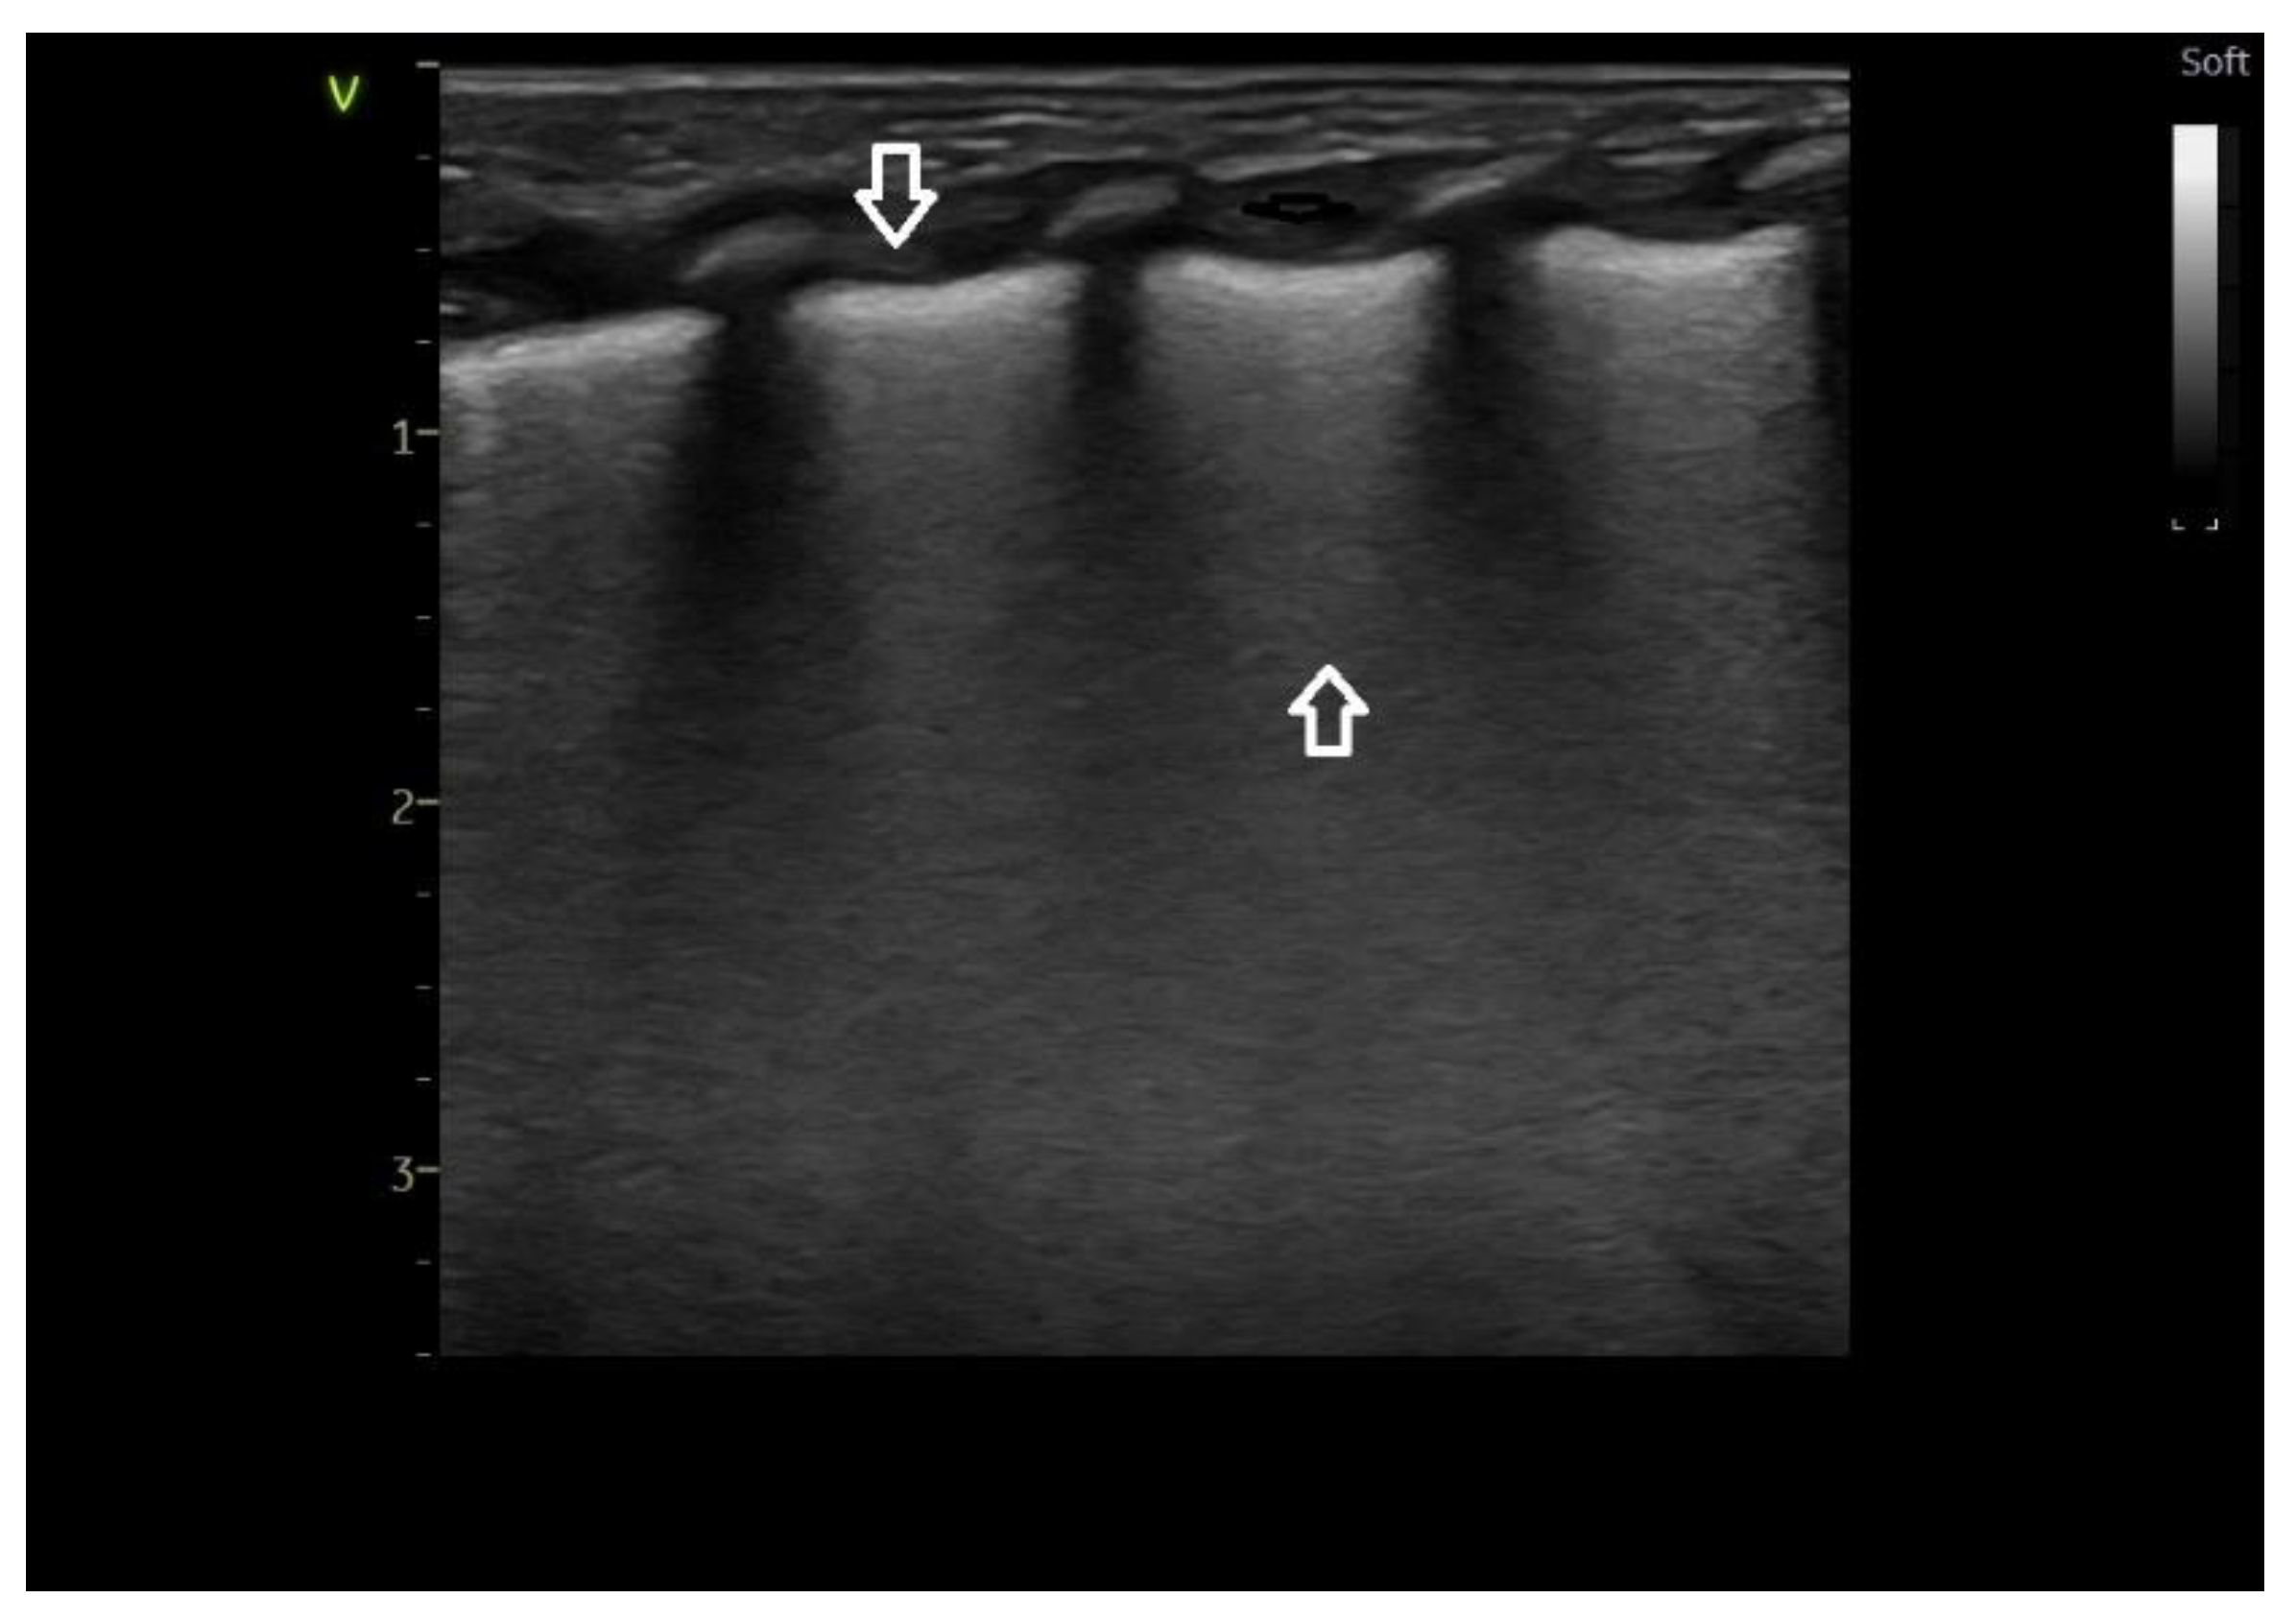

Lung ultrasound